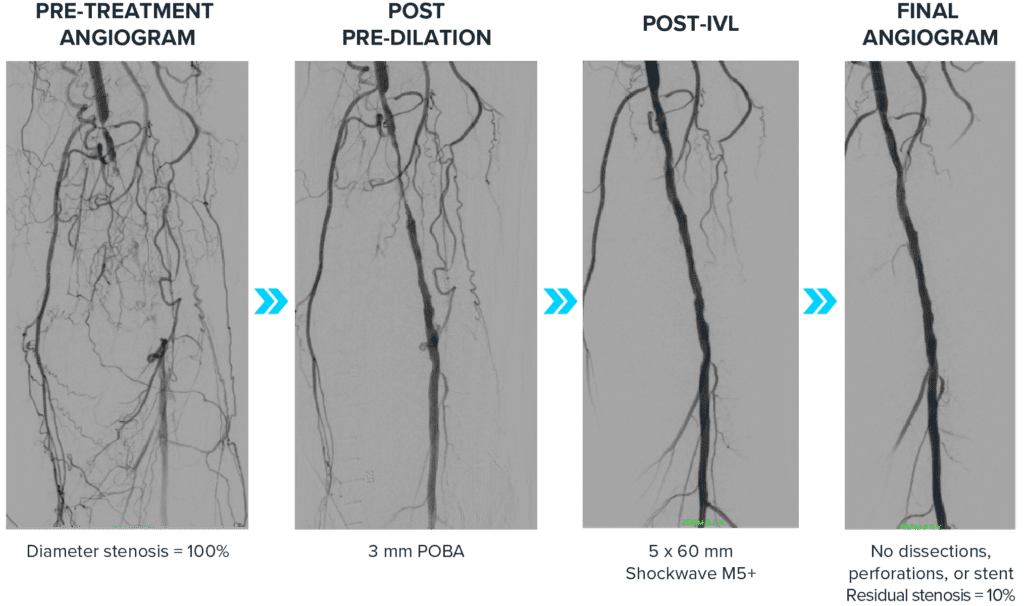

A 72-year-old female patient presented with lifestyle-limiting claudication and rest pain at night with worse symptoms in the left leg. The patient is a former smoker, has diabetes, CTO and chronic kidney disease (CKD). Invasive angiography of the left leg showed a chronic total occlusion in the P1 and P2 segments of the popliteal with no iliac disease and three vessel runoff to the feet. The CTO was crossed and a 3.0 mm POBA was used for the initial dilation. Then a 5.0 mm Shockwave M5+ was used along the calcified segments, finishing with a drug-coated balloon (DCB). Intravascular ultrasound (IVUS) imaging of calcified segments showed no dissections and good vessel expansion.